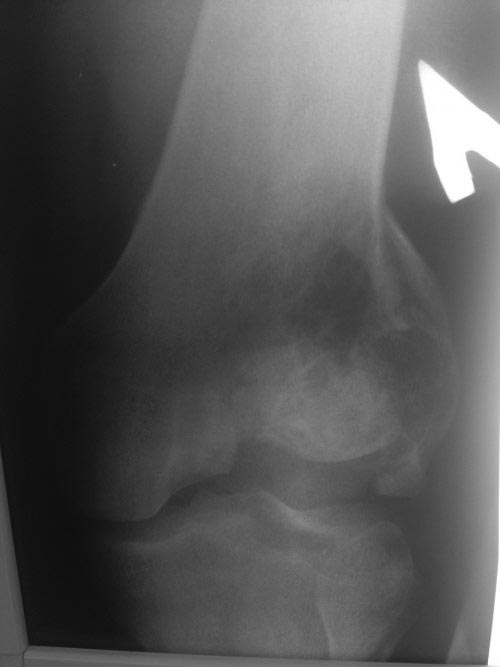

Второй случай, коллапс латерального мыщелка за счет стрессового перелома. До операции надо уточнить диагноз биопсией и определить границу поражения на КТ и МРТ. Здесь имеется вовлечение кортикального слоя и вряд ли дистракционный метод поможет восстановить контур мыщелка. Онкологический вариант замещения с удалением неплохой вариант, но агрессивный. Возраст молодой и при наличии костного банка можно было восстановить аллографтом. Сегодняшняя технология (3Д и КТ) позволяет подобрать идеальный размер целого мыщелка (аллографт).

Здесь представлен посттравматический дефект латерального мыщелка и лечение аллографтом.